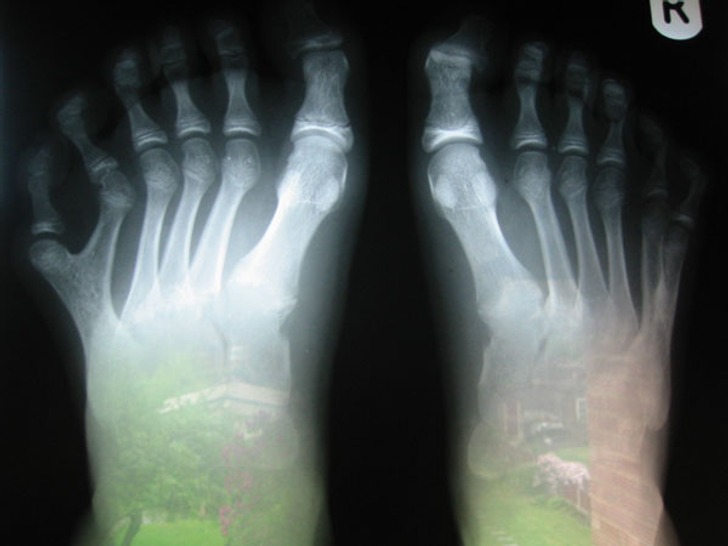

میرے بھائی کا ایکسرے جس کے پیروں میں 12 انگلیاں ہیں

اس آرٹیکل میں جو تصاویر موجود ہیں ان میں 5 سے زائد انگلیاں یا ایک انگلی میں 6 ناخن ہونا دراصل جینیاتی تبدیلیوں یا موروثیت کی وجہ سے ہوتا ہے۔ کچھ لوگ پیدائشی طور پر کم انگلیاں یا پھر زیادہ انگلیوں کے ساتھ پیدا ہوتے ہیں جن کا دواؤں سے یا پھر سرجری کے زریعے علاج کیا جاتا ہے۔